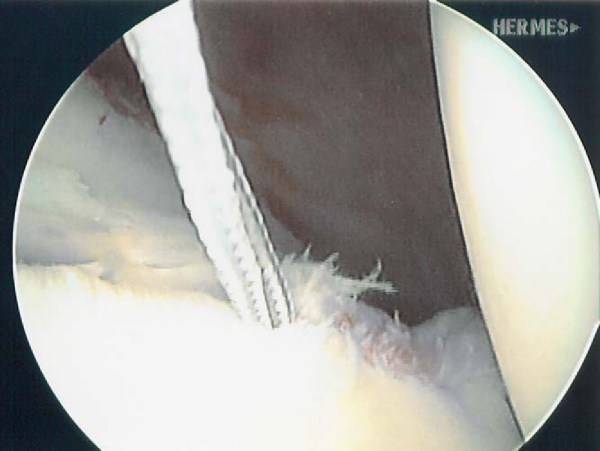

| • | A motorized synovial shaver or meniscal rasp is used to abrade the capsule adjacent to a labral tear and to débride and decorticate the glenoid rim to achieve a bleeding surface for capsular plication ( Fig. 9-1 ). |

2. Multi-Pleated Plication [15] [16]